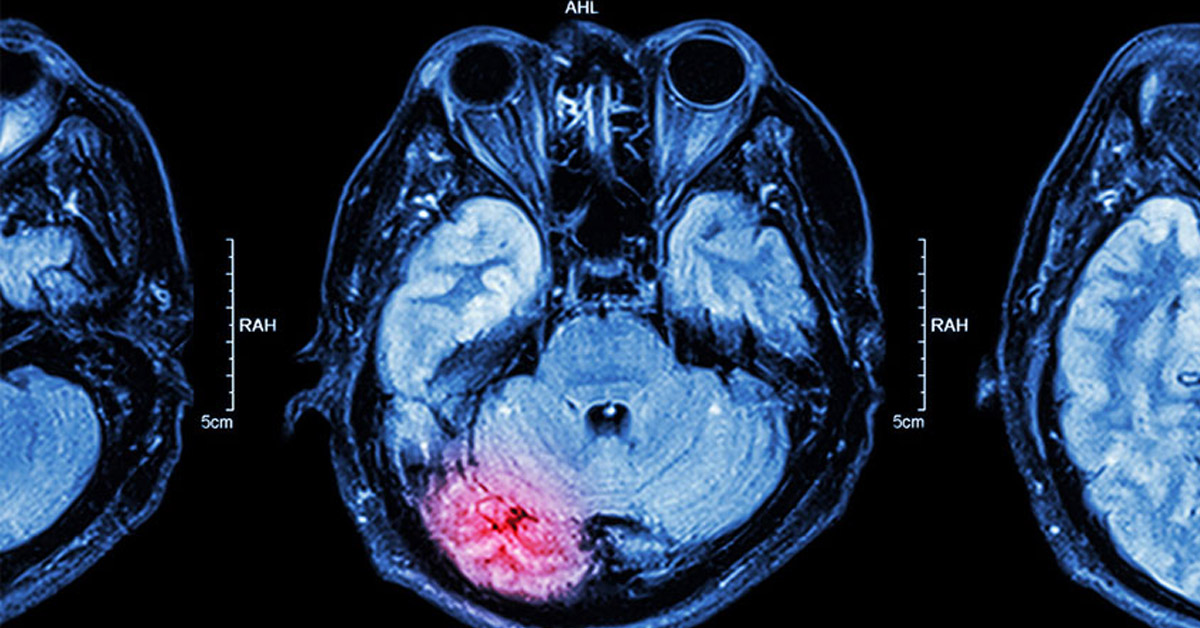

İnme, inflamatuvar ve iltihabi hastalıklar, epilepsi gibi nörolojik bozukluklar ve nörodejeneratif ( sinirlerde hasar yapan) hastalıkların hızlı ve erken tanısı, tedavi yapıldıysa tedavi sonrası başarıyı değerlendirmede ve sağkalımda önemlidir.

Merkezimizde bulunan son teknoloji cihazlar ve gelişmiş yazılımları sayesinde nörolojik hastalıklarda perfüzyon (kanlanma) incelemeleri yapılabilir, yüksek çözünürlüklü, 3 boyutlu (3D) görüntüler elde edilebilir.